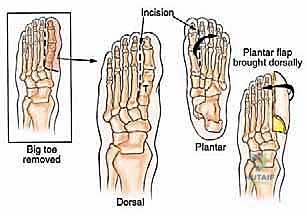

Metatarsophalangeal Joint Amputation

This is a more straightforward amputation when the tumor is confined to the toe or distal metatarsal head.

- Incision Planning: A longer plantar flap is planned. The incision is carried out at the level of the metatarsophalangeal joint on the dorsum of the foot.

- Dissection: Using sharp dissection, expose the MTP joint.

- Joint Disarticulation: The capsule, collateral ligaments, and flexor/extensor tendons are sharply cut at the level of the joint.

- Vascular Control: The digital vessels are identified and meticulously cauterized.

- Amputation: The toe is then removed.

- Flap Closure: The long plantar flap is brought over the dorsal aspect of the metatarsal head. The skin is repaired using 4-0 nylon sutures in an interrupted fashion, creating a smooth, non-tender, end-bearing stump.